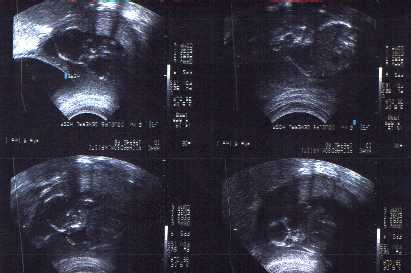

James Parker Richardson

August 22, 1998

Parker's first Interview